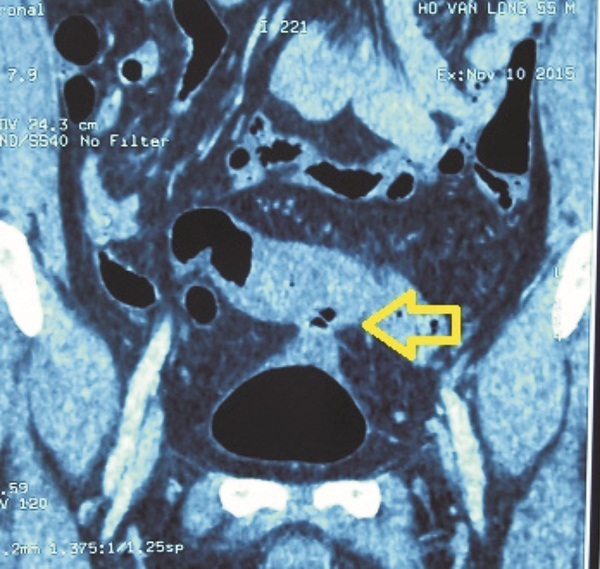

Chụp bàng quang bơm thuốc cản quang tan trong nước thấy thuốc đi vào đại tràng. Chụp đại tràng có thuốc cản quang không tan trong nước thấy thuốc vào bàng quang. Chụp CT bụng phát hiện có khối viêm dính từ đại tràng chậu hông vào bàng quang.

Chụp phim Cystography thấy thuốc ra ngoài bọng đái |